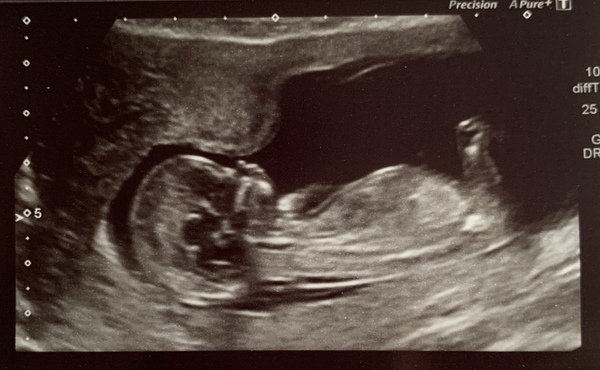

Here’s my little wriggler... measuring at 13+4, a full week later than I thought!! Has anyone else had this? How accurate is it?

Anyway all looks well and I feel so happy and lucky. Had blood test for screening today and that takes 2-3 weeks apparently!! 😩